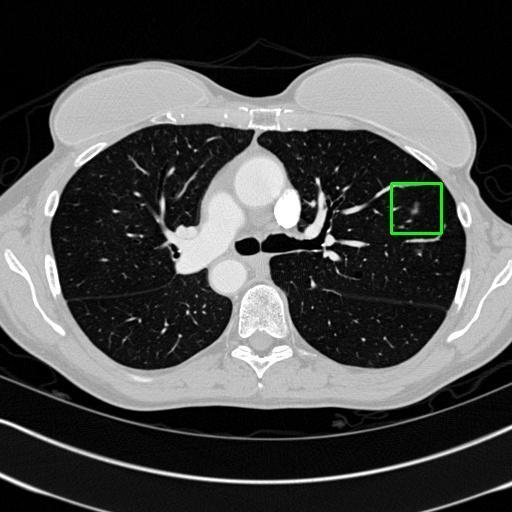

We developed an AI-based system using deep learning models for analyzing lung CT scans to detect and classify pulmonary nodules. We chose the YOLOv11 architecture for its enhanced object detection capability and adapted it specifically for medical imaging, incorporating pixel-level precision and severity classification.

Classification into three severity levels with colored bounding boxes.

Successfully built and deployed an AI model (YOLOv11) capable of detecting lung nodules in CT scans with high accuracy and real-time performance.

Designed a severity classification system that categorizes nodules into null, moderate, and severe using colored bounding boxes, assisting in rapid clinical decision-making.